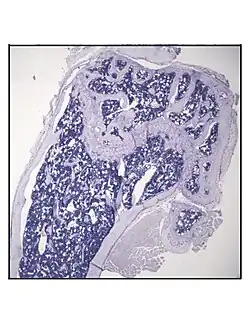

- Representative distal femur histologic section of a 16-week-old healthy C57BL/6 mouse demonstrating a typical quantity of marrow adipocytes.